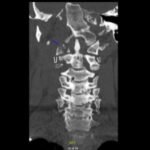

The Jefferson fracture classification system describes fractures of the atlas (first cervical vertebra or C1). Jefferson fractures with potential tears in the transverse ligament can cause cervical spine instability and can result in neurologic injury if not appropriately diagnosed and managed. We present the case of a 54-year-old man who fell head first with cervical spine tenderness and upper extremity paresthesias. The patient’s Jefferson fracture was diagnosed via computed tomography. The patient was then treated non-operatively for his Jefferson fracture, and he had an unremarkable hospitalization. Emergency physicians should obtain surgical consultation and consider the possibility of ligamentous injury in patients suffering injury to the cervical spine.